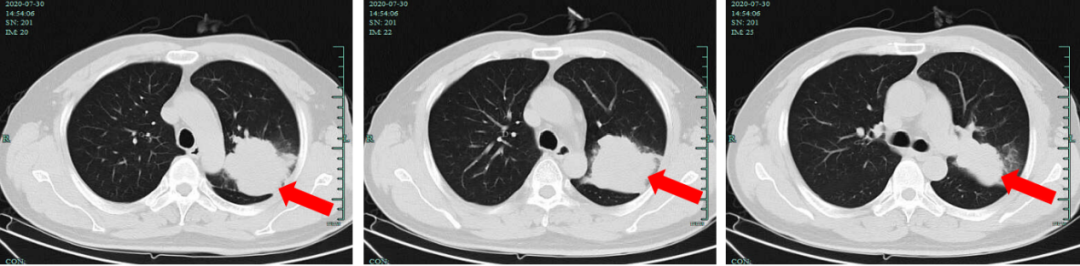

胸部CT平扫(2020-07-24):左肺上叶肿块,伴左肺上叶阻塞性炎症,肺癌首先考虑,建议穿刺活检。

图7:2020-07-30,基线期胸部增强CT